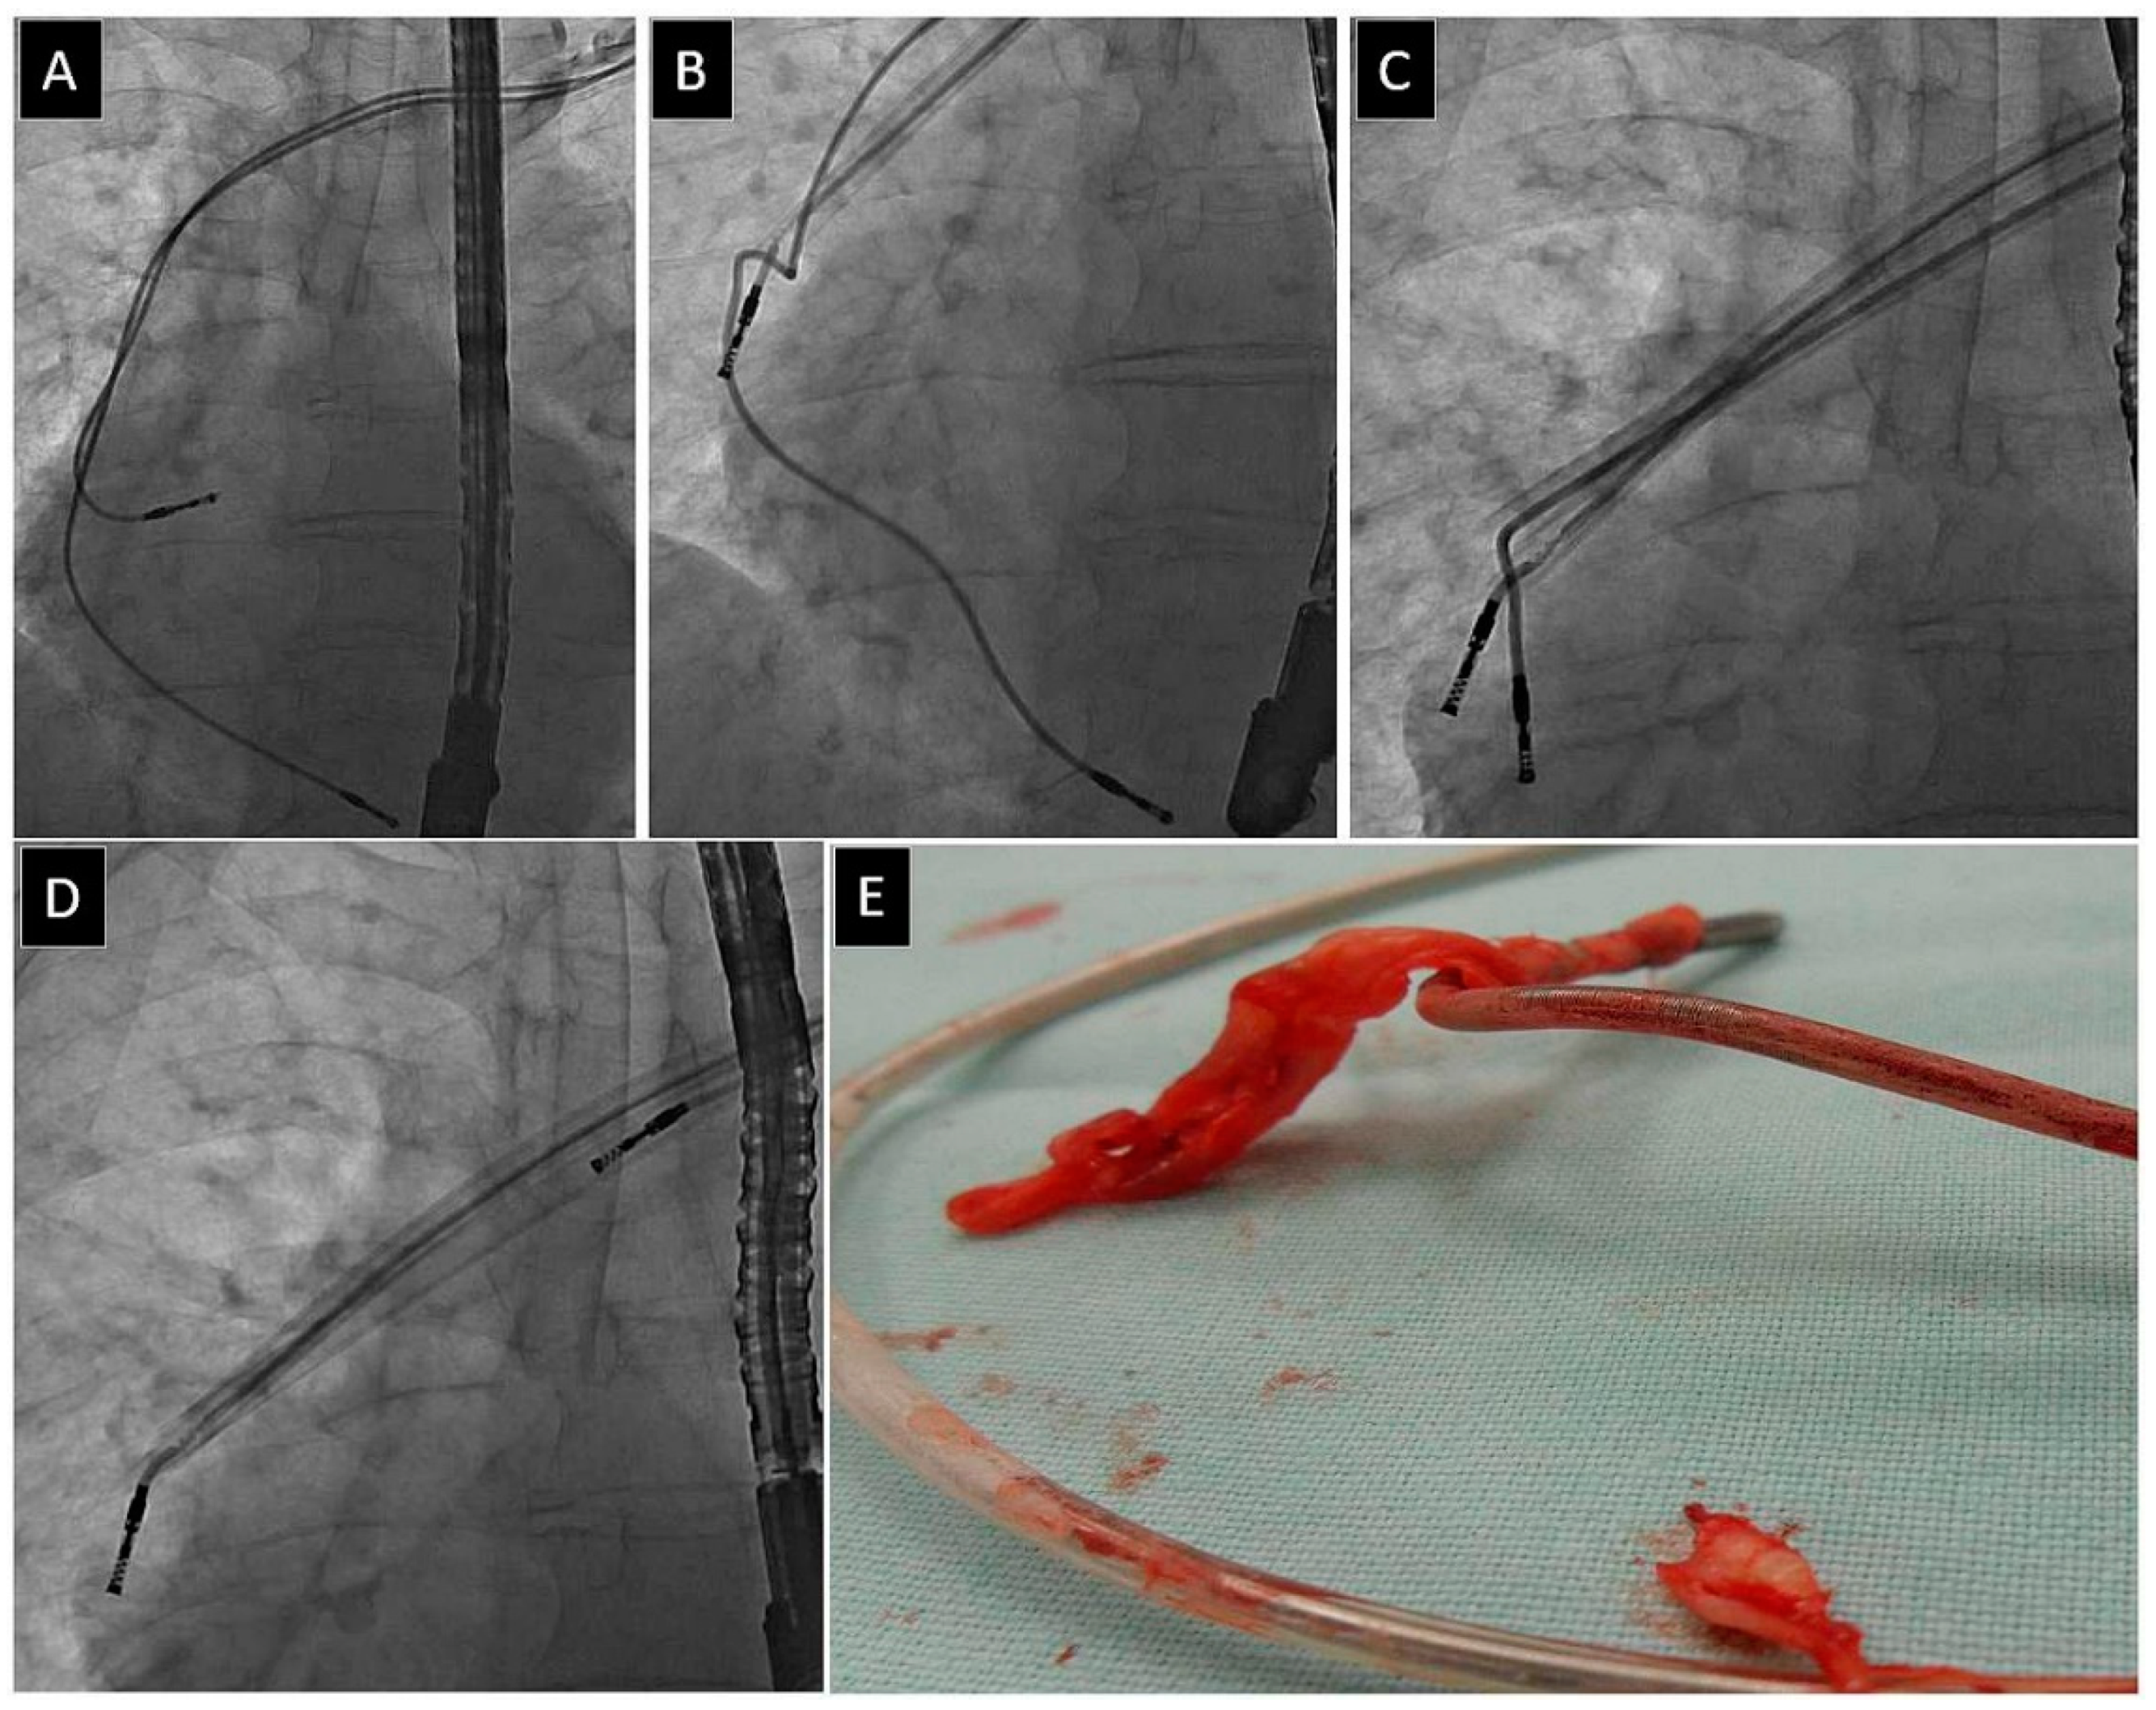

| Fracture of targeted lead * | 143 (3.84) | 58.7 8 ± 19.01 p = 0.001 | 43.25 ± 20.24 P=0.001 | 61 (42.66) P=0.201 | 52 (36.36) p = 0.001 | 55.05 ± 11.74 p = 0.001 | 3.59 ± 3.73 p = 0.001 | 42 (29.37) p = 0.950 |

| Fracture of targeted lead * | 143 (3.84) | 2.17 ± 0.85 p = 0.003 | 13 (9.09) p = 0.001 | 43 (30.07) p = 0.001 | 10 (6.99) p = 0.001 | 2.73 ± 1.40 p = 0.001 | 28 (19.58) p = 0.001 | 21 (14.68) p = 0.001 |

| Fracture of targeted lead * | 143 (3.84) | 2.04 ± 0.88 p = 0.001 | 34 (23.78) p = 0.001 | 13 (28.67) p < 0.001 | 41 (28.67) p = 0.001 | 134 (93.71) p = 0.001 | 185.5 ± 85.97 p = 0.001 | 28.53 ± 16.99 p = 0.001 |

| Fracture of targeted lead * | 143 (3.84) | 62.36 ± 52.38 p = 0.001 | 33.65 ± 32.26 p = 0.001 | 20 (13.99) p = 0.001 | 40 (27.97) p = 0.001 | 97 (67.83) p = 0.001 | 10 (6.99) p = 0.001 |

| Targeted lead fracture* | 143 (3.84) | 4.47 ± 6.54 p = 0.001 | 84 (58.74) p = 0.001 | 43.86 ± 22.64 p = 0.001 | 3.54 ± 0.73 p = 0.001 | 17.41 ± 7.21 p = 0.001 | 2.54 ± 0.71 p = 0.001 |

| Fracture of targeted lead * | 143 (3.84) | 12 (8.39) p = 0.001 | 8 (5.60) p = 0.001 | 1 (0.70) p = 0.001 | 4 (2.80) p = 0.473 | 7 (4.90) p = 0.001 | 61 (42.66) p = 0.001 |

| Fracture of targeted lead * | 143 (3.84) | 76 (53.15) p = 0.001 | 0 (0.00) p = 0.565 | 0 (0.00) p = 0.368 | 2 (1.40) p = 0.281 | 12 (8.39) p = 0.201 | 48 (33.57) p = 0.241 |